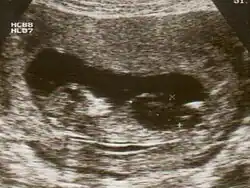

| Ultrasound of fetus with Down syndrome showing a large bladder | |

Fetal megacystis[1] is a rare disease that is identified by an abnormally large or distended bladder.

Fetal megacystis is diagnosed during pregnancy by ultrasound imaging procedures. Since it can be associated with genetic abnormalities, further ultrasounds and tests may be administered during pregnancy. It may also be diagnosed as megalocystis, and/or termed megabladder, which is the same condition.